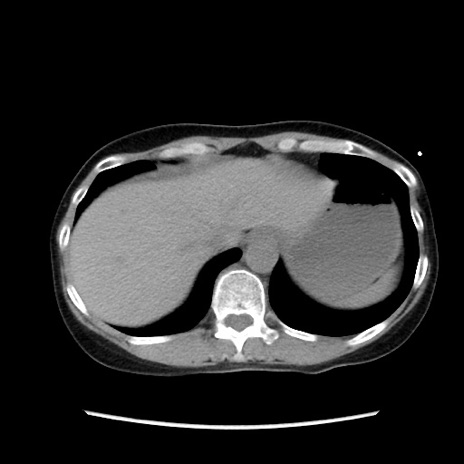

症例32(横断像)

【症例】40歳代 女性

【主訴】上腹部痛、嘔気・嘔吐

【現病歴】約9時間前頃から急に上腹部痛、嘔気、嘔吐が出現。改善しないため救急要請。

【既往歴】子宮頚癌(広汎子宮全摘術、放射線療法)、腸閉塞

【身体所見】腹部:平坦、軟、腸雑音亢進、上腹部を中心に腹部全体に圧痛あり。

【データ】WBC 8400、CRP 0.03